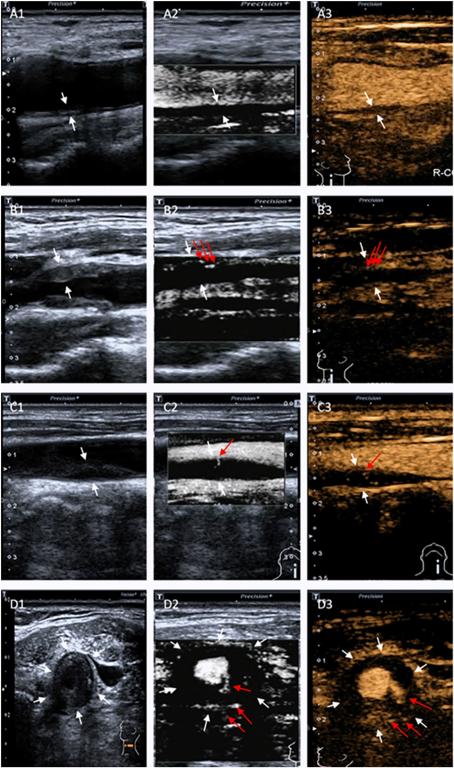

圖1 常規超聲、SMI及超聲造影分級

研究結果顯示兩名超聲醫師在應用SMI和CEUS方法診斷頸動脈斑塊新生血管方面高度一致。SMI與超聲造影評價頸動脈斑塊的新生血管分級結果一致。SMI和CEUS分級與斑塊厚度呈正相關。研究表明CEUS和SMI對評估斑塊的新生血管有很高的診斷價值。